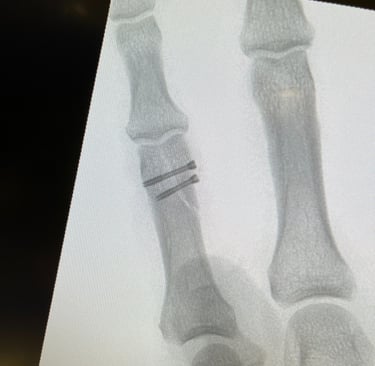

Polso e Mano

Mi occupo del trattamento delle principali patologie della mano e del polso, sia degenerative che traumatiche. Tratto condizioni frequenti come sindrome del tunnel carpale, dito a scatto, tendiniti e traumatologia della mano e del polso, con approccio conservativo o chirurgico mirato al recupero della funzionalità e alla riduzione del dolore.